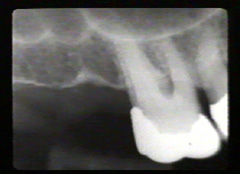

Las radiografías periapicales muestran pérdida de hueso alveolar en aproximadamente la mitad de la longitud de la raíz. La pérdida de hueso en el área de furacación se indica por la radiolucidez aumentada en la unión de las raíces en la región cervical.

Los premolars han perdido más de la la mitad de la longitud de la raíz del hueso alveolar periodontal.  Hay defectos infraóseos en particular en el segumdo premolar en mesial y distal. El modelo semilunar que cubre la raíz del segundo premolar también indica la presencia de una defecto óseo en palatino.